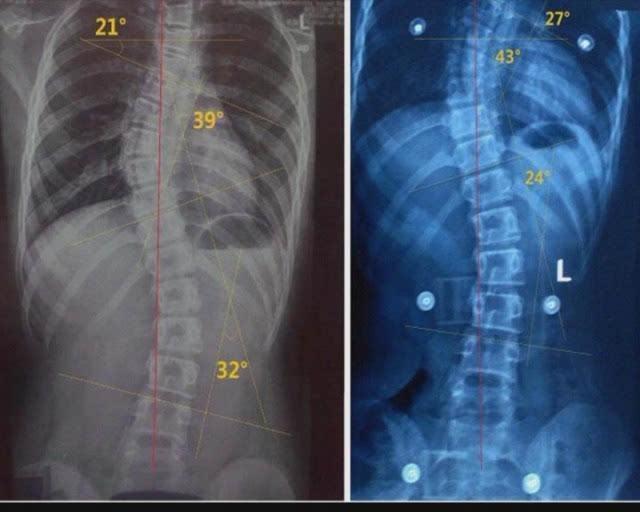

一转眼,宝宝已经6个月了,楠楠决定带着宝宝去做一次体检,看看宝宝发育得如何。通过这次检查,医生发现了一个大问题,医生对楠楠说:“你家宝宝脊柱变形了,可能会影响以后的健康。”楠楠有点不敢相信医生所说的话,宝宝平时看上去很健康,不哭也不闹,脊柱怎么会变形呢?医生仔细分析了一下,发现了问题所在,原来,宝宝的奶奶为了方便省事,整天都让宝宝躺在婴儿车里,而楠楠买的这个婴儿车质量不是特别好,宝宝长期躺在里面,所以才会出现脊柱变形的情况。